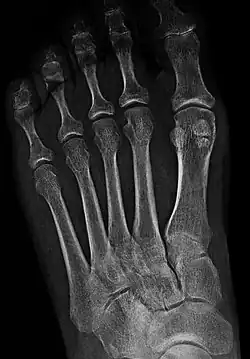

![]() Sesamoid bones at the distal end of the first metatarsal bone of the foot. | |

- In the foot—the first metatarsal bone usually has two sesamoid bones at its connection to the big toe (both within the tendon of flexor hallucis brevis).[10] One is found on the lateral side of the first metatarsal while the other is found on the medial side. In some people, only a single sesamoid is found on the first metatarsal bone.